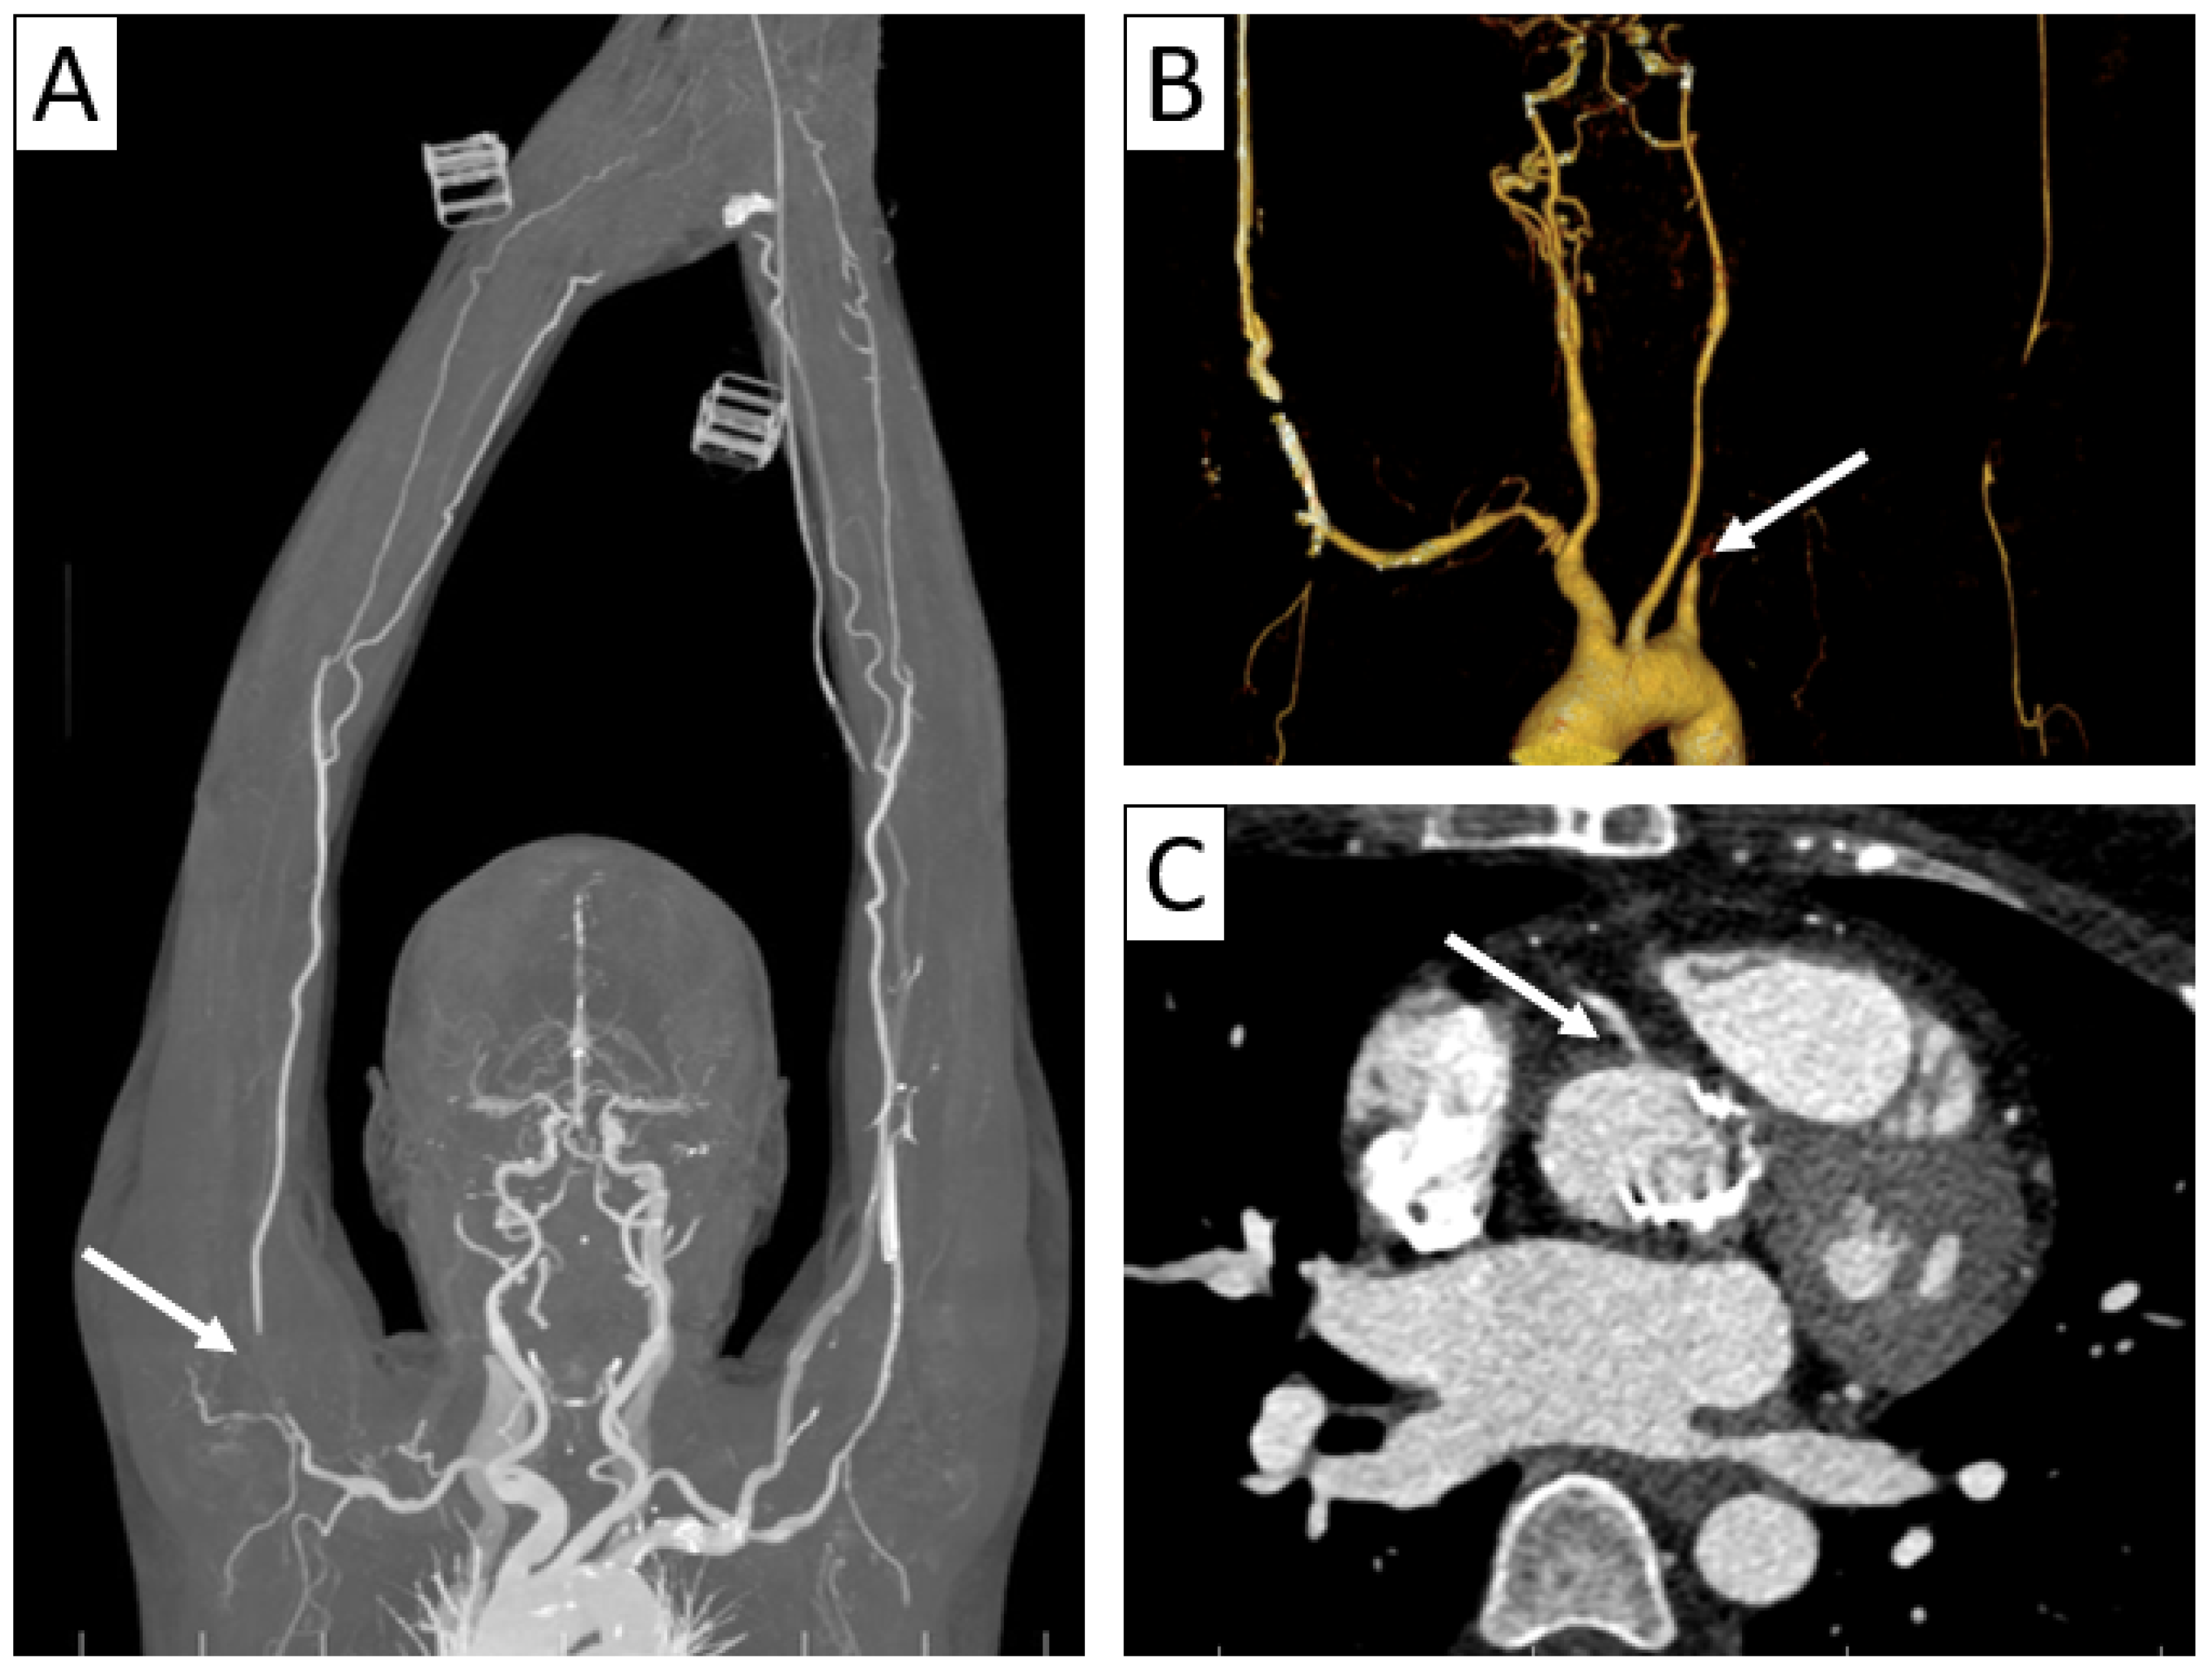

| CTA | Circumferential parietal thickening Vessel wall enhancement | Circumferential parietal thickening Vessel wall enhancement Luminal stenosis or narrowing |